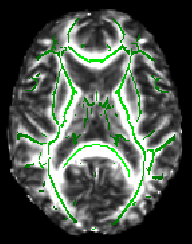

The script finishes by telling you to check whether a suitable threshold for the mean FA skeleton is 0.2 (a typical value used by the next script). For example, load the 4D FA data and the skeleton into FSLView:

cd stats

fsleyes all_FA -dr 0 0.8 mean_FA_skeleton -dr 0.2 0.8 -cm green

The -dr option sets sensible display range options, and in the case of the skeleton image, also controls the thresholding applied. Now turn on the movie loop; you will see the mean FA skeleton on top of each different subject's aligned FA image. If all the processing so far has worked ok the skeleton should look like the examples shown here (see the TBSS paper for more examples of different subjects' results underneath the skeleton). If the registration has worked well you should see that in general each subject's major tracts are reasonably well aligned to the relevant parts of the skeleton. If you set the skeleton threshold (in FSLeyes, the lower of the display range settings) much lower than 0.2, it will extend away towards extremes where there is too much cross-subject variability and where the nonlinear registration has not been able to attain good alignments. Remember the skeleton threshold for the next stage.